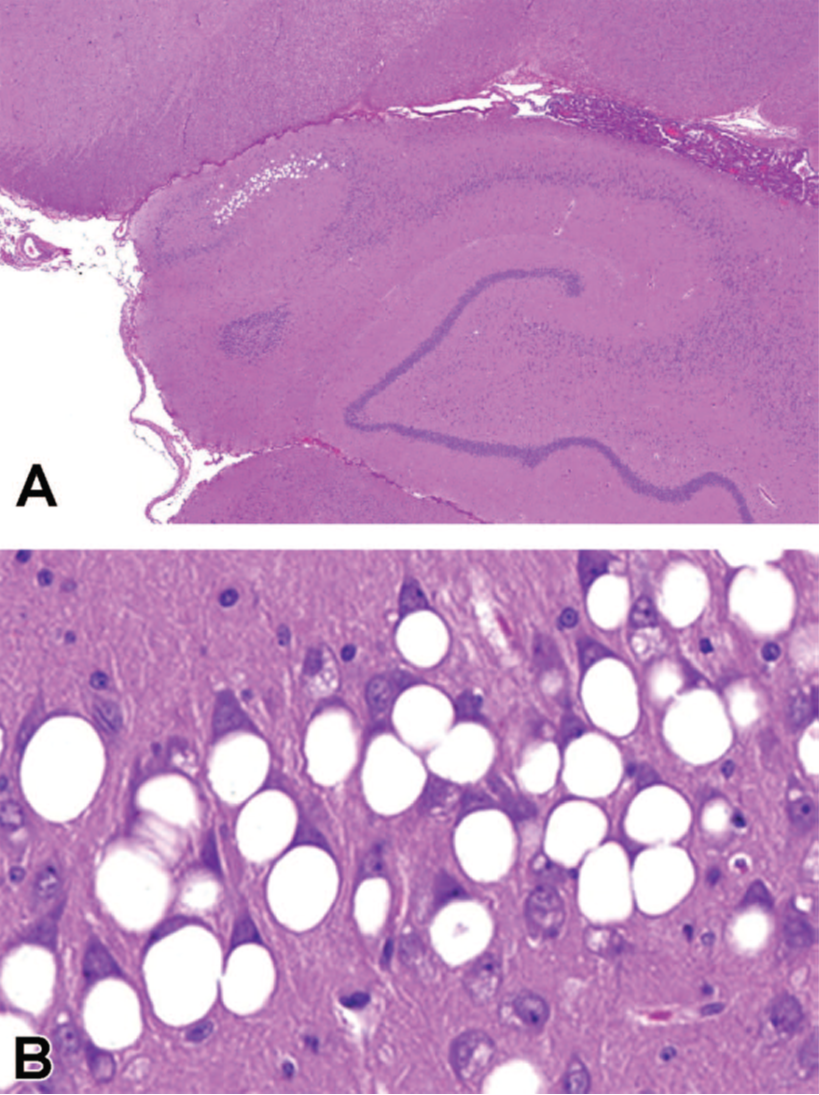

非人类灵长类动物(NHP)的海马区HE切片。通过5次35mg反义寡核苷酸(ASO)

毒性研究中腰椎穿刺超过13周。大液泡在鞍角1区(CA1)的锥体神经元中观察

(A)高倍镜下,单个、大、清晰的“大泡”

(B)神经元中的液泡经常将细胞核挤压移位到细胞外围。